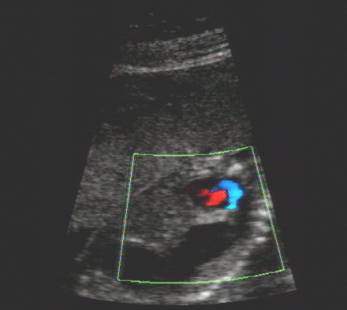

Stomach in left chest cavity

Note the absence of significant cardiac displacement.

This would be unusual in diaphragmatic hernia.